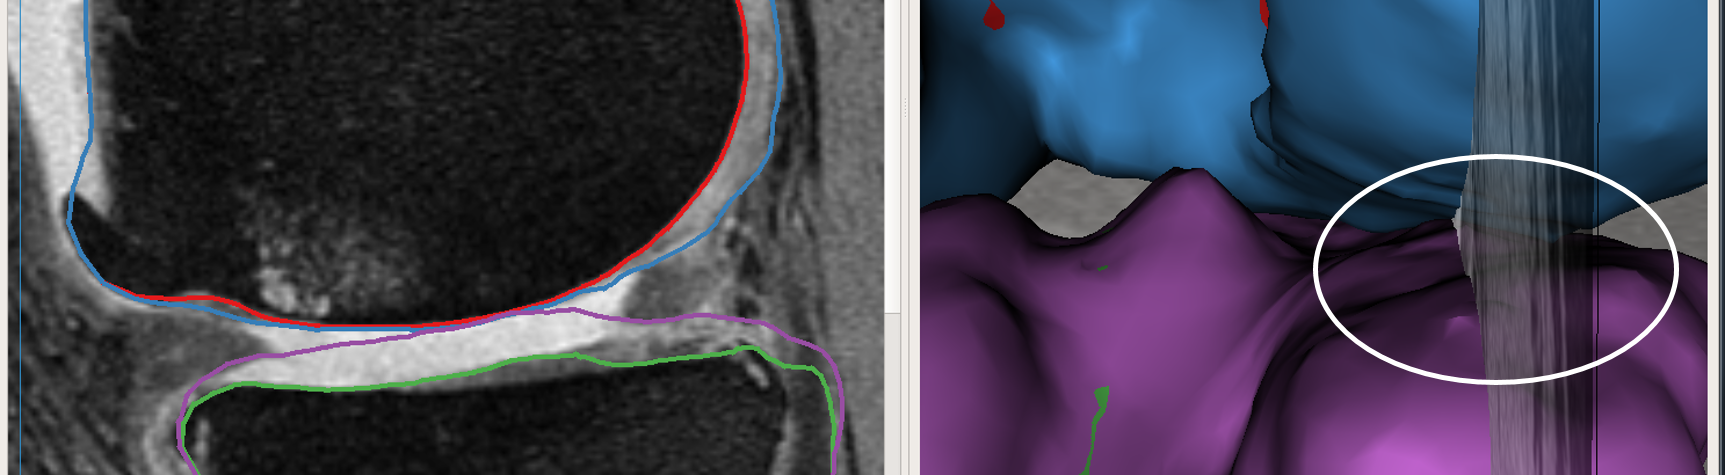

The above work-flow is repeated to correct the tibial cartilage errors as well. In the intermediate steps following the correction of the femur, the tibia bone and cartilage surfaces appear to worsen. This can be attributed to a combination of the existing graph costs and the graph constraints. Since the tibia cartilage surface has no clear defined edge cost in that region, the surface result moved along with the femur corrected cartilage surface. Subsequently due to the inter-surface distance constraints between the tibial surfaces the tibial bone surface also changed. However once the nudge points provided the appropriate locations for cost modification the erroneous surfaces were corrected (Figs. 3c,d). Note that the corrections made on a single 2D slice resulted in the entire locally affected 3D neighborhood being corrected. This can be appreciated in the corresponding circled regions of the surface model.